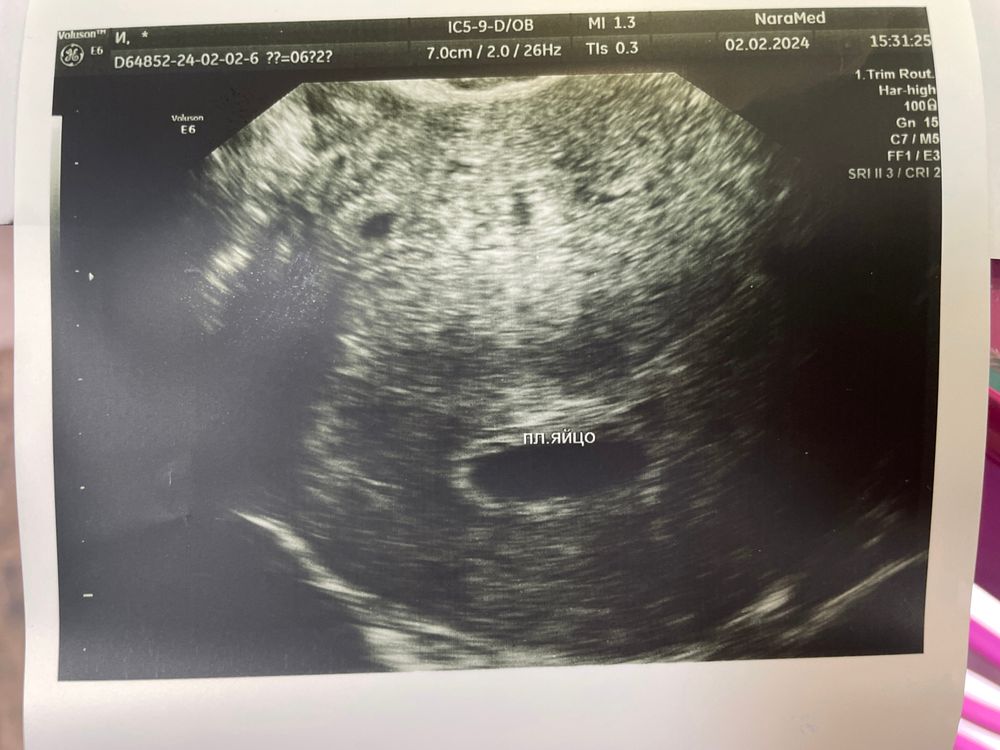

Первая беременность, не видно эмбрион

Ждите до 20 мм Диагноз анэмбрионии (пустое плодное яйцо) предполагается, если в плодном яйце размером 20 мм не определяется желточный мешок. Или если плодное яйцо диаметром более 25 мм с желточным мешком не содержит эмбриона. А также при размере желточного мешка 10 мм и более

Тетя Кошка, спасибо большое, ждем… тем более оно сейчас еще и неправильной формы… по одной стороне 13, по второй всего 5… Ждем и верим 🙏🏻🙏🏻🙏🏻

Марина, ну вот сегодня не увидели ничего 😔😔😔 только овальной формы яйцо и всё…